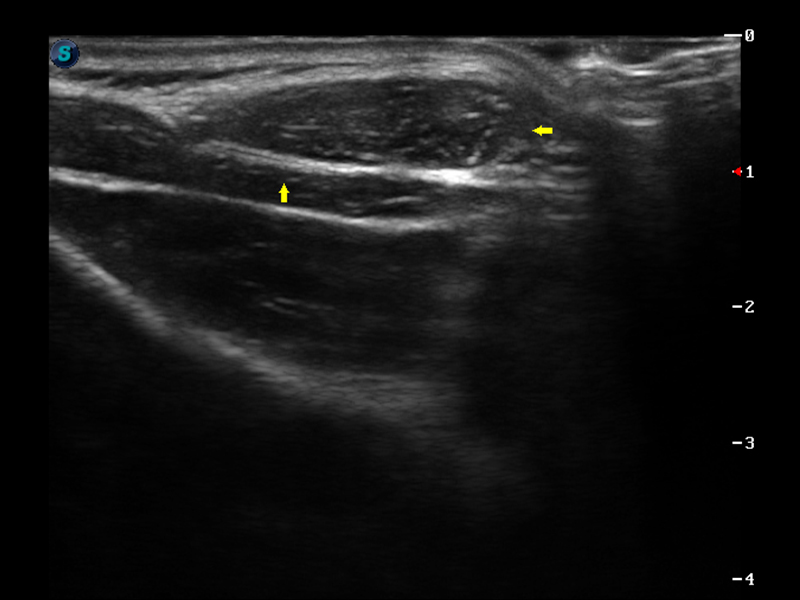

S9便携式彩色多普勒超声诊断仪是16877太阳集团研发的高端便携彩超设备,外观设计新颖、产品性能卓越。S9在便携超声领域采用了突破传统的触摸屏交互设计,并以先进的软件硬件技术和设计理念,为您带来清晰的图像质量、稳定的工作性能和便捷的操作体验。

μ-Scan微米成像